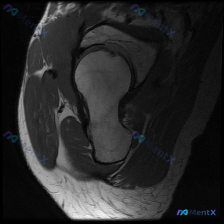

看到一个髋关节MRI病例,先给大家分享一下核心发现: 影像类型:髋关节MRI冠状位T1加权成像 主要表现:股骨头及股骨颈近端骨髓呈弥漫性T1低信号,与正常脂肪骨髓的高信号形成鲜明对比;髋臼顶轮廓清晰,关节间隙无明显狭窄,盂唇在T1序列上未见明确撕裂征象。 患者主诉提到了“盂唇病变”,但影像核心是骨髓...